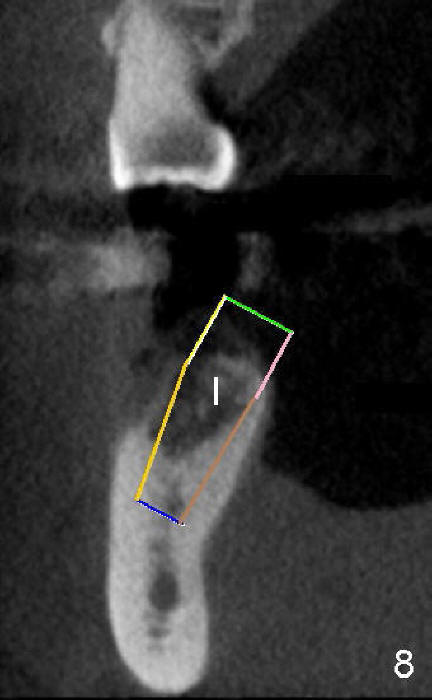

五十多岁的吴先生右下六有根分叉感染(图一),有一次到外地出差疼痛难忍拔除了,一两年后才同意植牙,图二显示已经愈合近远中(M, D)牙槽窝,六乘十七毫米植牙(图三I)好像种得很端正,其实并不完全是这样。让我们回到图二,沿着虚线做个冠状切面,显示右上六号牙以及右下六牙槽骨(图四*),与对侧六号牙冠状切面(图五)对比,右下六牙槽骨往舌侧(L)倾斜(B:颊侧),要植入长而宽的植牙,它就往舌侧倾斜(图八)。为了与对侧牙齿咬合,必须用二十度倾斜的基牙(图六A),但是临床上通过基牙而改变的角度还不够(图七),所以最后牙冠(图十C)不在植牙(I)长轴上,也就是一部分牙冠是悬臂的(*),容易造成陶瓷断裂,基牙松动。避免悬臂牙冠最好的方法便是拔牙后即刻植牙(图九),如果骨质已经吸收,植骨(图十一红色)或者骨扩张时尽量让颊侧骨板往颊侧移动,纠正植牙倾斜角度。